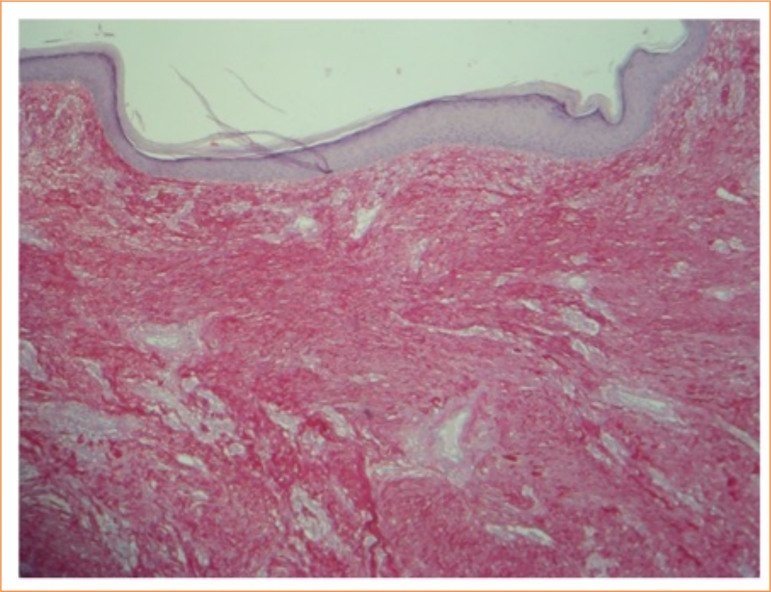

Purpose: Keloids are unaesthetic benign dermatosis characterized by a disorganized proliferation of collagen. Treatment of keloids constitutes a therapeutic challenge. The aim of this study was to evaluate the efficacy and effectiveness of topical imiquimod associated with surgical excision in the treatment of keloid.

Abstract Image